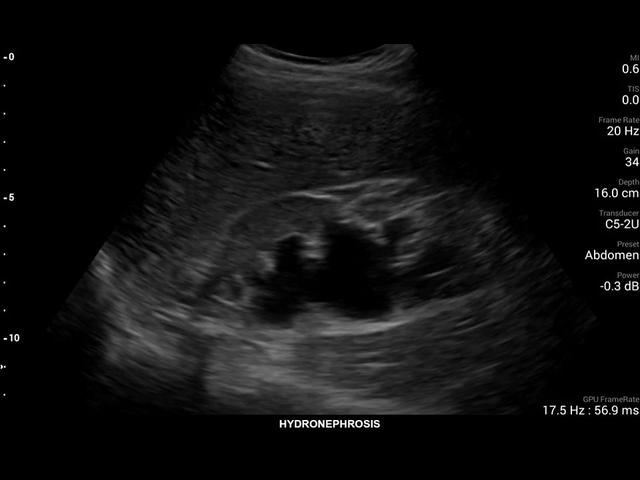

• Конвексный УЗИ датчик Philips C5-2